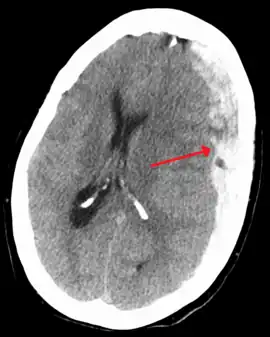

Subdural hematomas occur most often around the tops and sides of the frontal and parietal lobes.[3][2] They also occur in the posterior cranial fossa, and near the falx cerebri and tentorium cerebelli.[3] Unlike epidural hematomas, which cannot expand past the sutures of the skull, subdural hematomas can expand along the inside of the skull, creating a concave shape that follows the curve of the brain, stopping only at dural reflections like the tentorium cerebelli and falx cerebri.

On a CT scan, subdural hematomas are classically crescent-shaped, with a concave surface away from the skull. However, they can have a convex appearance, especially in the early stages of bleeding. This may cause difficulty in distinguishing between subdural and epidural hemorrhages. A more reliable indicator of subdural hemorrhage is its involvement of a larger portion of the cerebral hemisphere. Subdural blood can also be seen as a layering density along the tentorium cerebelli. This can be a chronic, stable process, since the feeding system is low-pressure. In such cases, subtle signs of bleeding—such as effacement of sulci or medial displacement of the junction between gray matter and white matter—may be apparent.

Fresh subdural bleeding is hyperdense, but becomes more hypodense over time due to dissolution of cellular elements. After 3–14 days, the bleeding becomes isodense with brain tissue and may therefore be missed.[20] Subsequently, it will become more hypodense than brain tissue.[21]